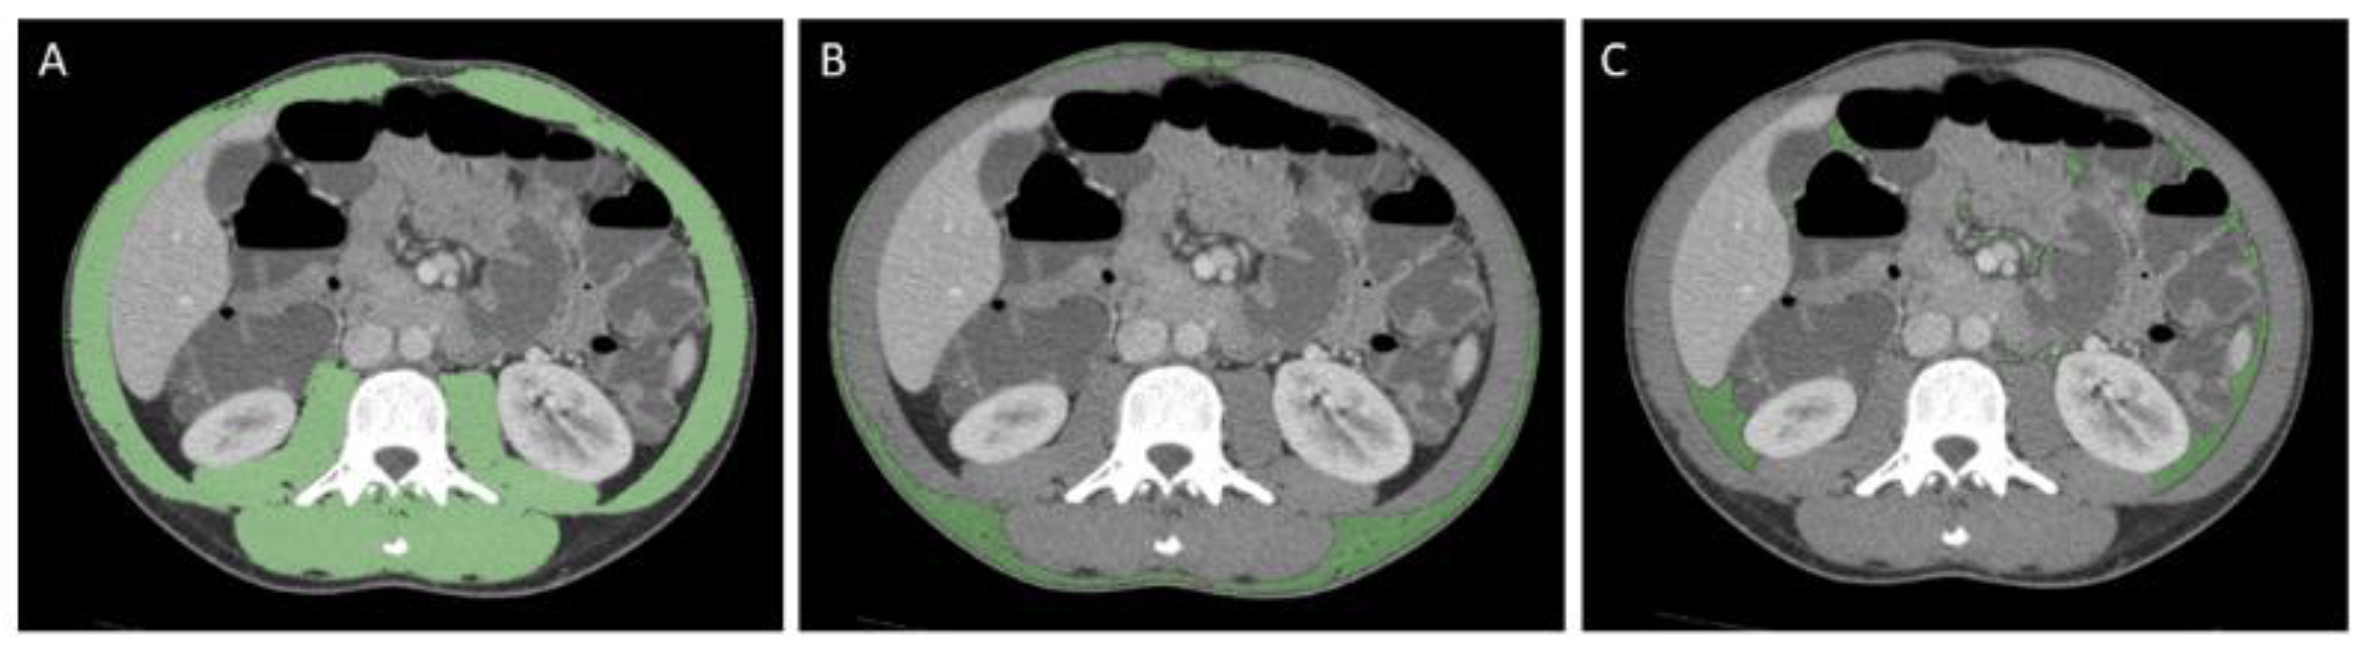

2.1. Sarcopenia, Nutritional Status, and Body Composition Assessment

2.3. Image Analysis